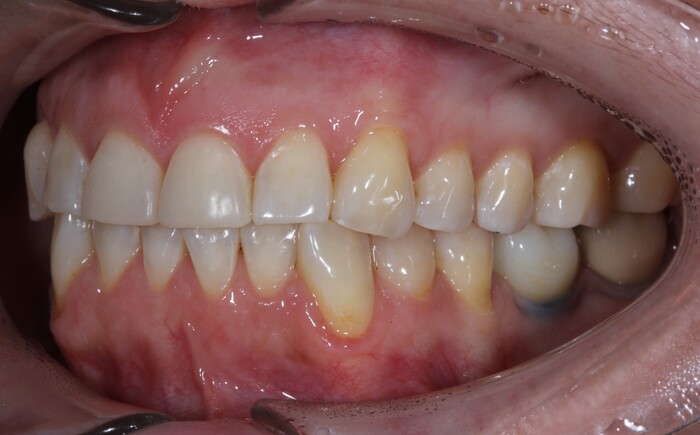

Что по текущей ситуации: по прежнему ни о каком смыкании зубов речи и не идет, контактирует только по одному жевательному зубу с каждой стороны. Но я к этому привыкла и жую настолько, насколько получается. Опять же, стараюсь слишком волокнистое и твердое не кушать. Все равно не прожую и застрянет. Речь вполне нормальная, но как и прежде долго говорить красиво не получается: устает челюсть, мышцы и текут слюни :DDD

Губы по прежнему не смыкаются (см фото ниже), рот в 99% времени приоткрыт. Сохнут зубы, язык, слизистые. Но я водохлеб, так что местами жить можно)) Самое дурацкое это сейчас, когда наступают холода - эти зубы мерзнут! И это таааак неприятно, и иногда даже больно. Прям брррр!